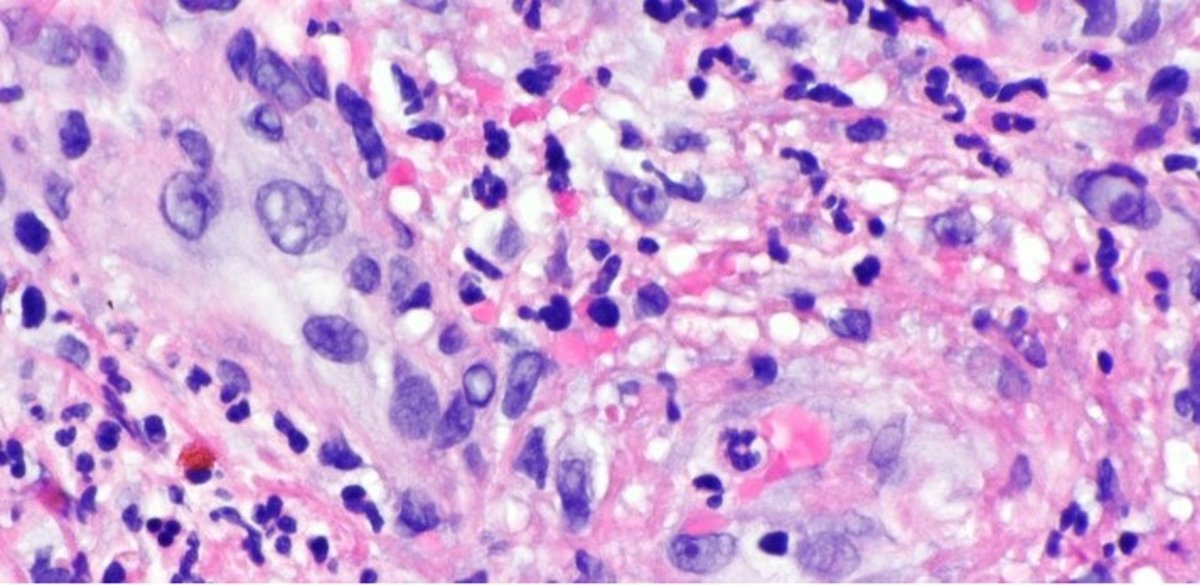

Células afectadas por vasculitis linfocítica.

Células afectadas por vasculitis linfocítica. - WIKIMEDIA.